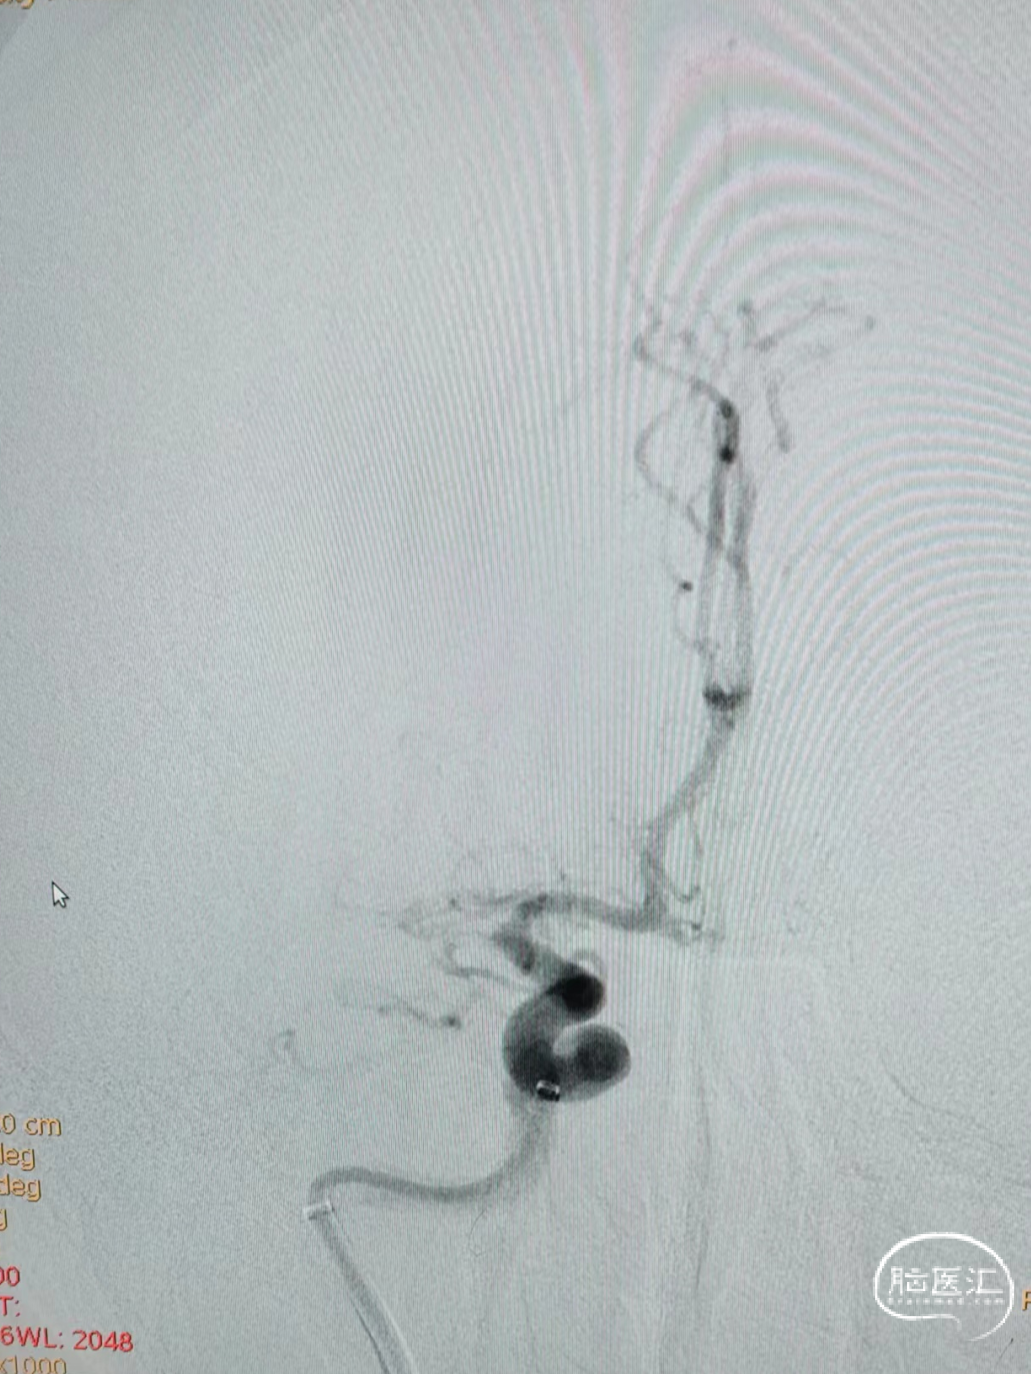

右侧颈内动脉造影示:后交通动脉以上颈内动脉闭塞。

经过抽吸导管抽吸后造影见颈内动脉通畅,大脑前动脉显影,但大脑中动脉仍然闭塞。

0.021in Headway微导管超选越过闭塞段后微导管造影。